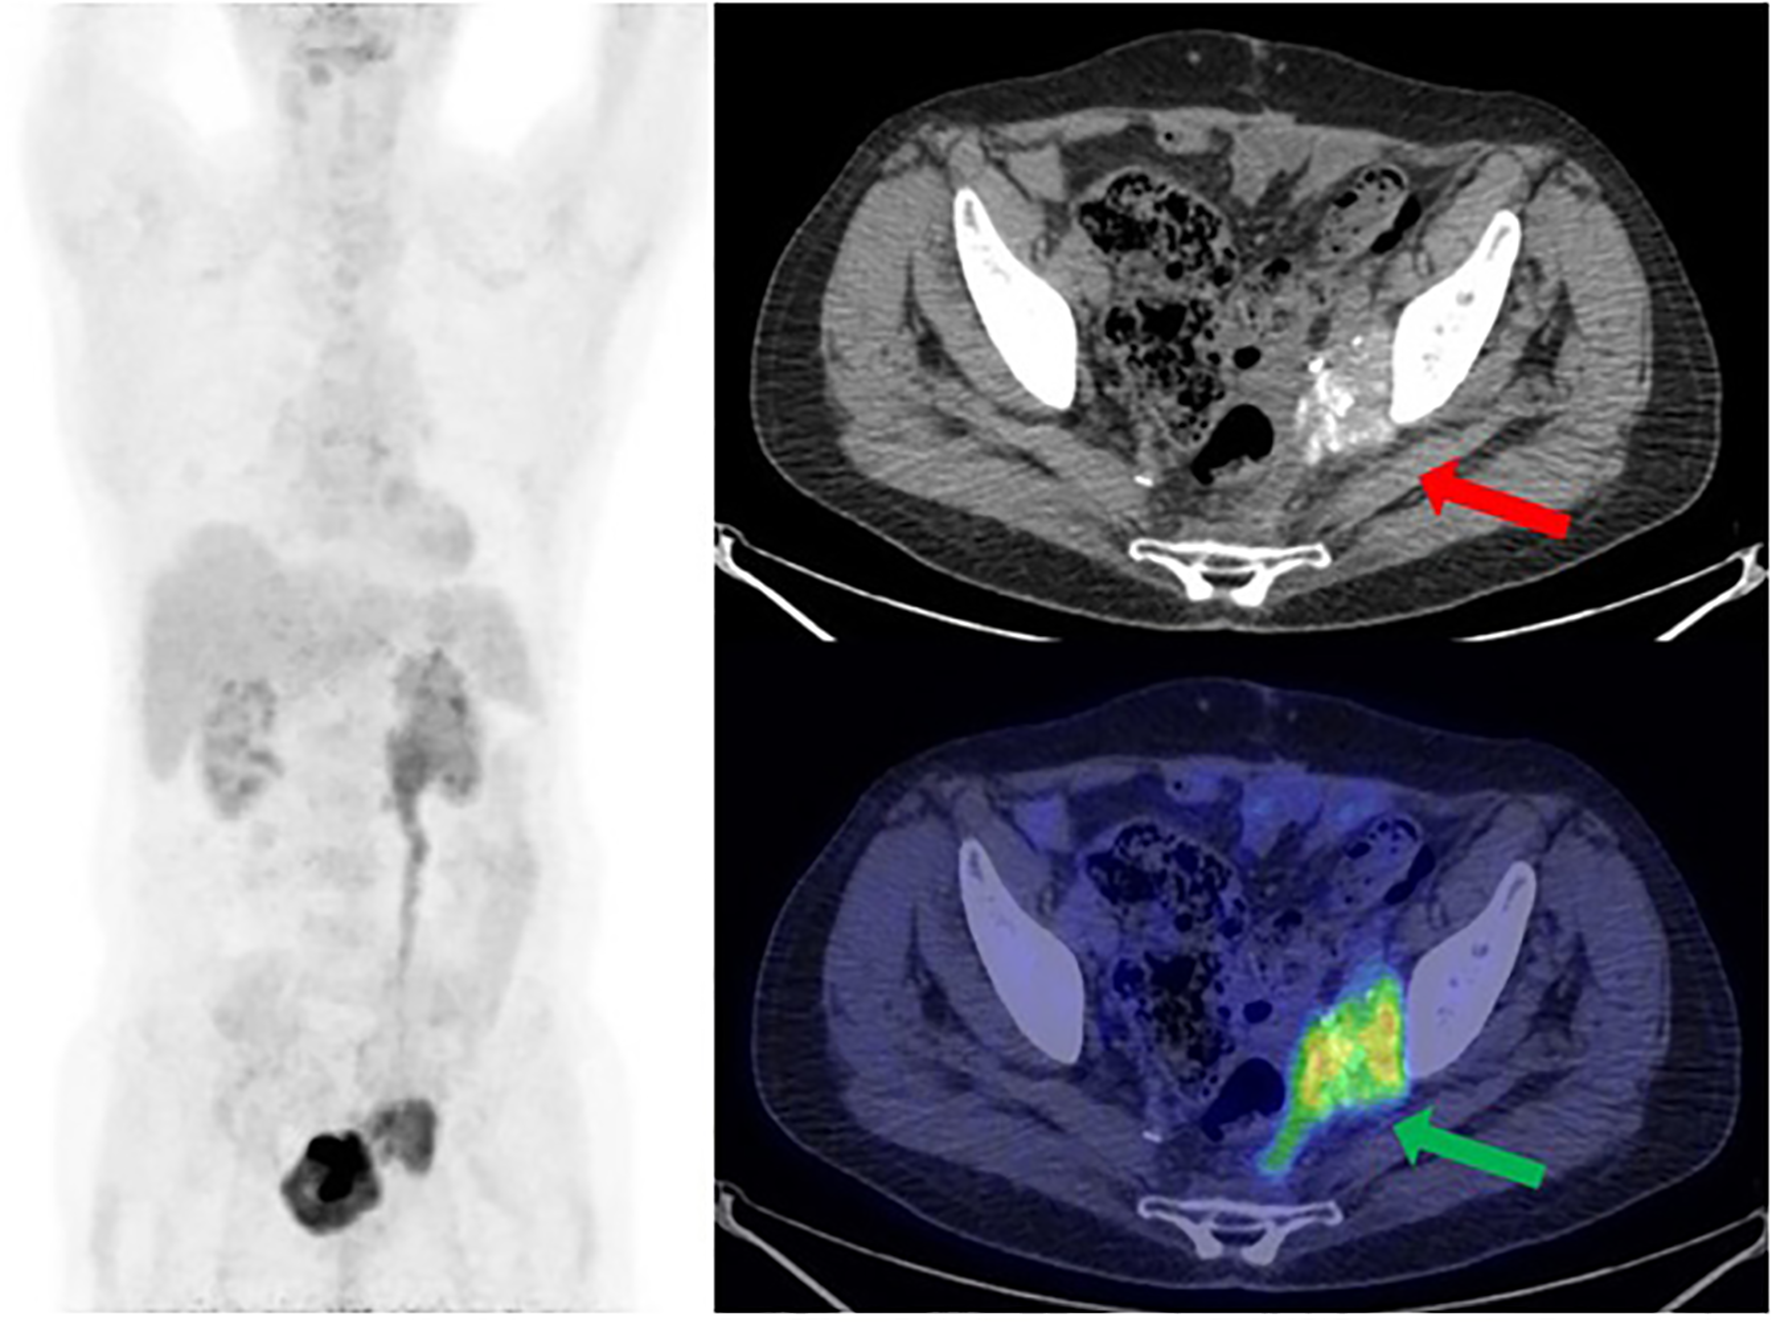

One year later, a follow-up CT scan shows a left obturator and peri-bladder neoformation of 4 cm. PET/CT documented radiopharmaceutical hyperaccumulation at the left obturator (mSUV of 7.7) (Figure 3). These lesions were also evident at CT of co-registration.

Figure 3

[18F] FDG PET/CT MIP reconstruction and transaxial image (performed at the University Hospital of Bari) showed the recurrence of disease at the left side of the pelvis, near the bladder, with a size of 3.7 × 4.8 cm and an mSUV of 7.7 (green arrow). Note the psammomatous bodies (concentric calcifications, a consequence of apoptotic cell desquamation—red arrow), a typical feature of ovarian tumors, which confirm the Mullerian origin of this man’s tumor.